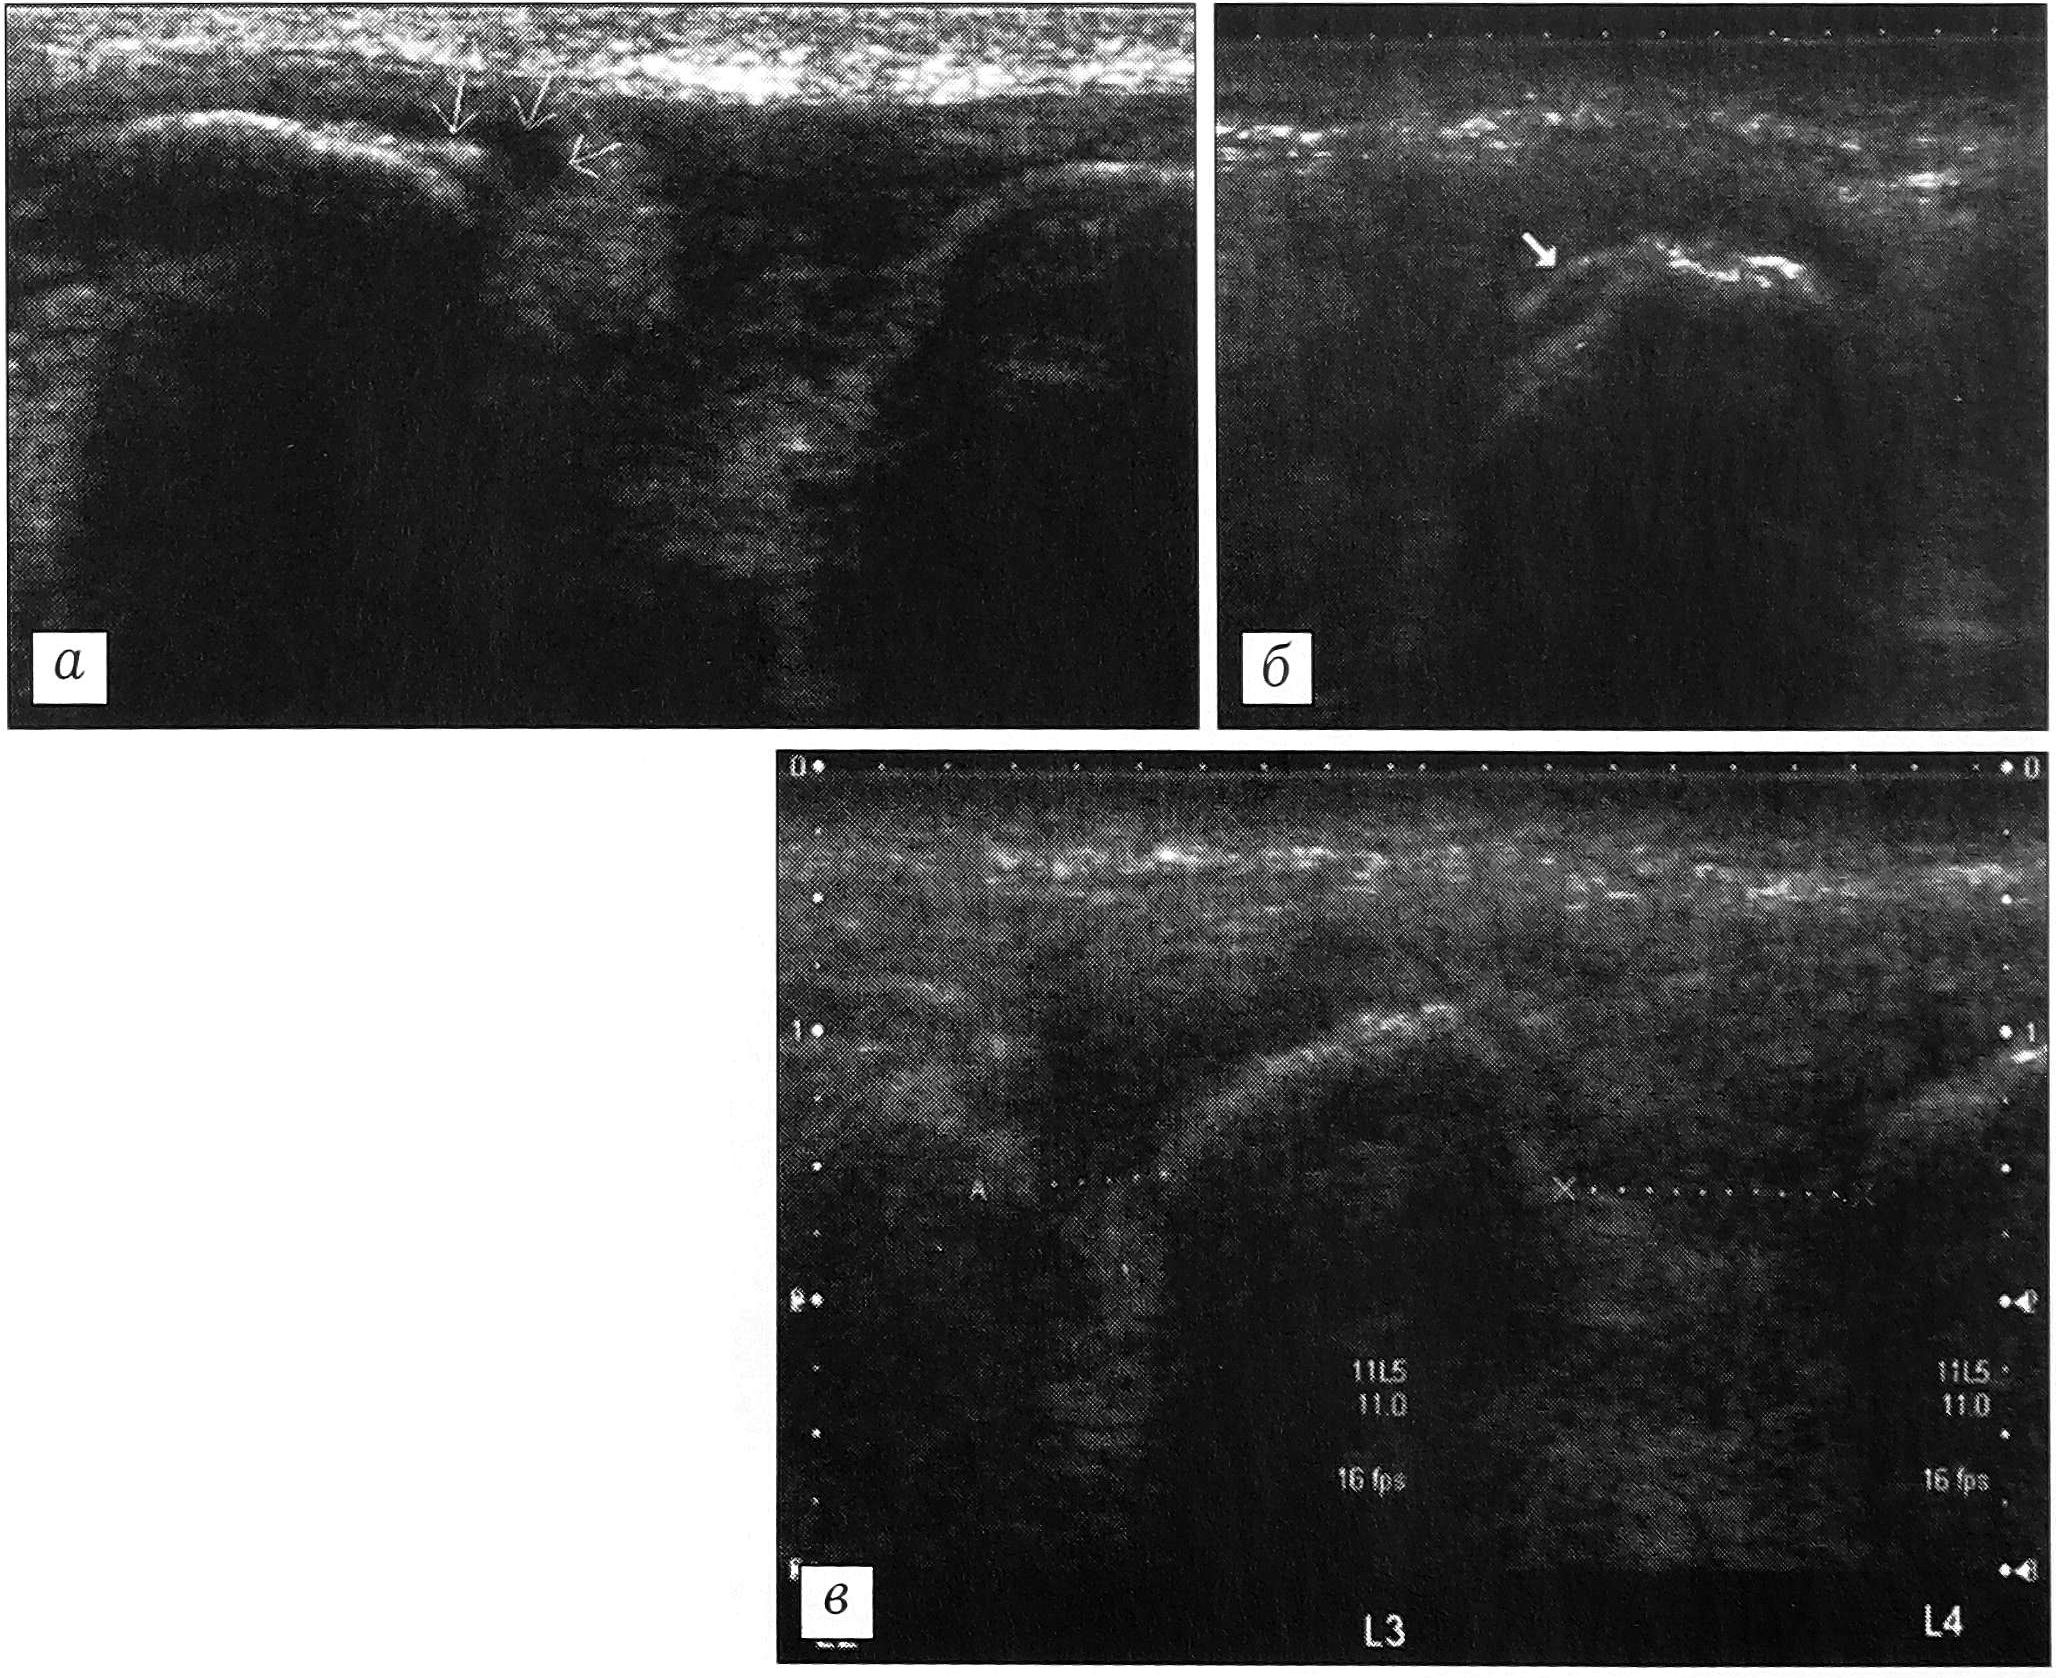

Межостистые связки при сонографии имеют вид плотноволокнистых структур, расположенных между остистыми отростками. Более плотный задний край их — надостистая связка. При хронической перегрузке остистых связок определяются рубцовые изменения надостистых и межостистых связок, кальцификаты в их толще и оссификаты в местах костных прикреплений (рис. 5, а). В 2 случаях обнаружен лигаментоз надостистой связки (рис. 5, б). Рентгенологически при этом наблюдались признаки синдрома Бааструпа. Наличие дефекта в остистой связке, увеличивающегося при сгибании позвоночника, подтверждает диагноз разрыва связки.

Как показал анализ полученных данных, длина остистых связок, или величина межостистого промежутка, весьма индивидуальна. Вместе с тем у каждого пациента длина остистых связок в поясничном отделе позвоночника практически не различается (разница составляет в среднем 0,06 мм). Поэтому оптимальным является сравнение длины остистых связок у одного и того же обследуемого. При хронической микротравматизации связок отмечаются увеличение межостистого промежутка, выраженные дегенеративные изменения связок (рис. 5, в).

Рис. 5. Ультрасонограммы остистых связок поясничного отдела позвоночника. а — рубцовые изменения, кальцификаты межостистой связки; б — лигаментоз надостистой связки; в — удлинение остистых связок вследствие повторных микротравм.